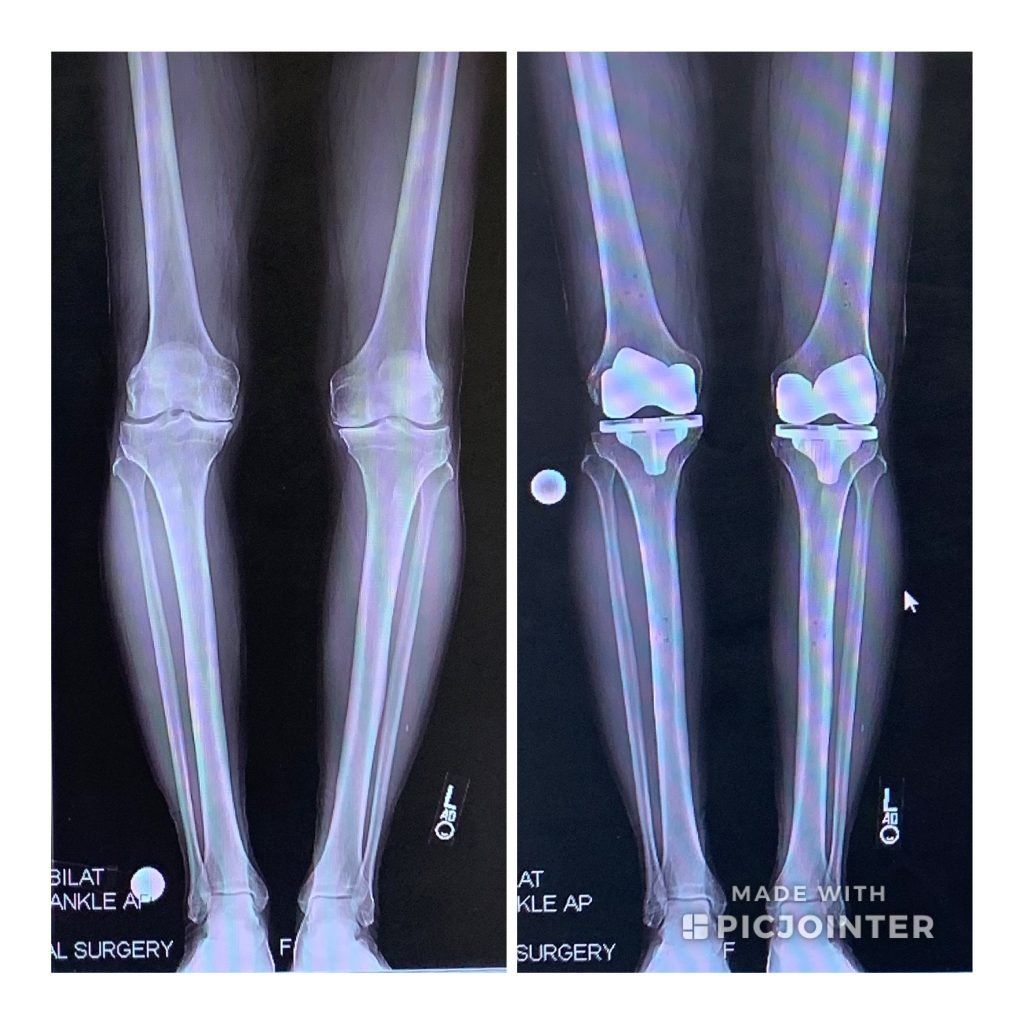

Expert Advice on Bilateral Knee Replacement

After years of chronic, debilitating arthritis knee pain that was impacting my quality of life in too many ways, I decided to consider knee replacement surgery. After consulting with Dr. Buly I made the life changing decision to have bilateral total knee replacement surgery in June 2015. My experience at HSS was tremendous. The surgical staff, nursing care and physical therapy team were all special. My pain was carefully managed and my PT progress was steady. After a summer of rigorous PT I was back coaching football and teaching a full course load. The next spring I was back on the tennis court and golf course, hiking, walking the dog for five miles a day and enjoying a new life. I haven't felt this young in over ten years. Life is good.